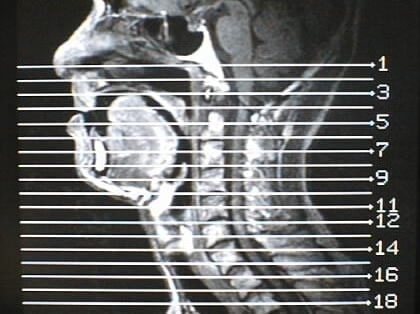

MRI画像比較

中咽頭末期がんMRI画像①

入院当時MRI画像①